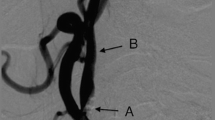

It was only possible to attempt filter implantation on both sides in 23/25 (92%) of patients due to poor imaging quality bilaterally (1 patient) and to previously unrecognized atheromatous plaque in the CCA on one side (1 patient). In the remaining 23 patients, the overall rate of initial successful deployment on the initial attempt was 47 out of 56 filters (84%). In the 9 patients with an initially unsuccessful implantation attempt, all devices (100%) were immediately retracted successfully using the pulling wire, and successful re-implantation was then performed. There were no major adverse events during the procedure. Of the 24 patients receiving an implant (23 bilaterally and one unilaterally), 24, 22, and 20 patients completed 3, 6, and 12 months follow-up, respectively (3 device-unrelated deaths and 1 patient lost to follow-up). No major device-related adverse events were seen during follow-up. Of the 47 implants (in 24 patients) that were properly positioned by the end of the procedure, all 47 (100%) remained properly positioned at all subsequent follow-ups. A typical X-ray image of bilateral correct filter positioning post implantation is shown in Fig. 8.